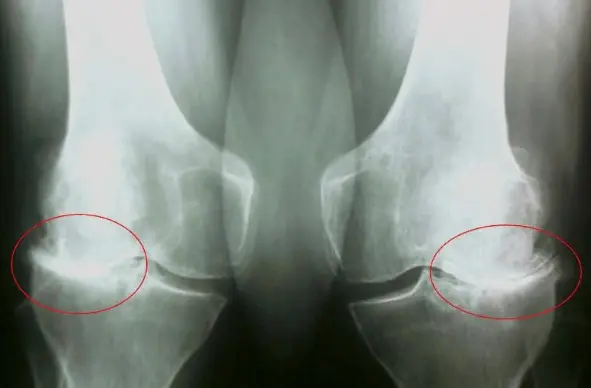

এই ছবিগুলো দেখো। সঠিক ছবিতে, জয়েন্টের জায়গা নেই, হাড়গুলো একে অপরের সাথে ঘষছে, যার ফলে তীব্র ব্যথা হচ্ছে। আর এই প্রক্রিয়া বন্ধ করা খুব কঠিন! কয়েক বছরের মধ্যে, ব্যক্তিটি অক্ষম হয়ে যাবে এবং নিজের যত্ন নিতে পারবে না।